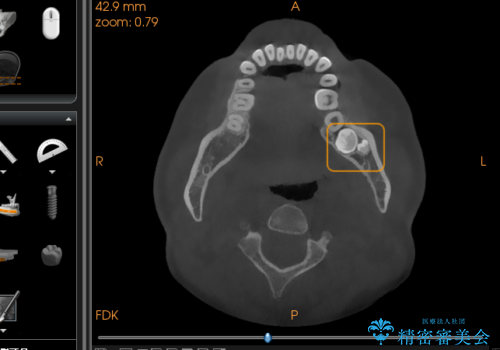

2. 【埋伏智歯と埋伏智歯の過剰歯の抜歯】埋まっている親知らず2本の抜歯の治療中

2.